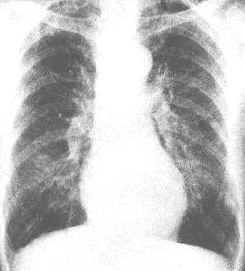

診斷:對嚴重胸部鈍性創傷的病人,來急診時即有嚴重呼吸困難和發紺,查體發現張力性氣胸、氣胸、縱隔氣腫和下頸部氣腫有重要意義,即使無氣胸也是X 線胸像上提示氣管破裂的最敏感的徵象。最可靠的診斷氣管破裂的方法是纖維支氣管鏡檢查。所有臨床上懷疑有氣管損傷的病人,如情況允許,均應立即行纖維支氣管鏡檢查來確立診斷,以防延誤診斷造成死亡或並發其他問題。張力性氣胸和氣胸安置胸腔閉式引流後,發現大量氣體持續外漏,隨吸氣動作而加重,根據上述體徵也可確診,病情平穩後,立即做X 線胸片證實診斷。對大多數無並發大咯血的病例,不必急於做支氣鏡檢或其他檢查。其他輔助檢查:

胸CT2.氣管CT 斷層檢查 可發現氣管斷裂的直接徵象,氣管透亮帶的變形及不連續,甚至有錯位的徵象。